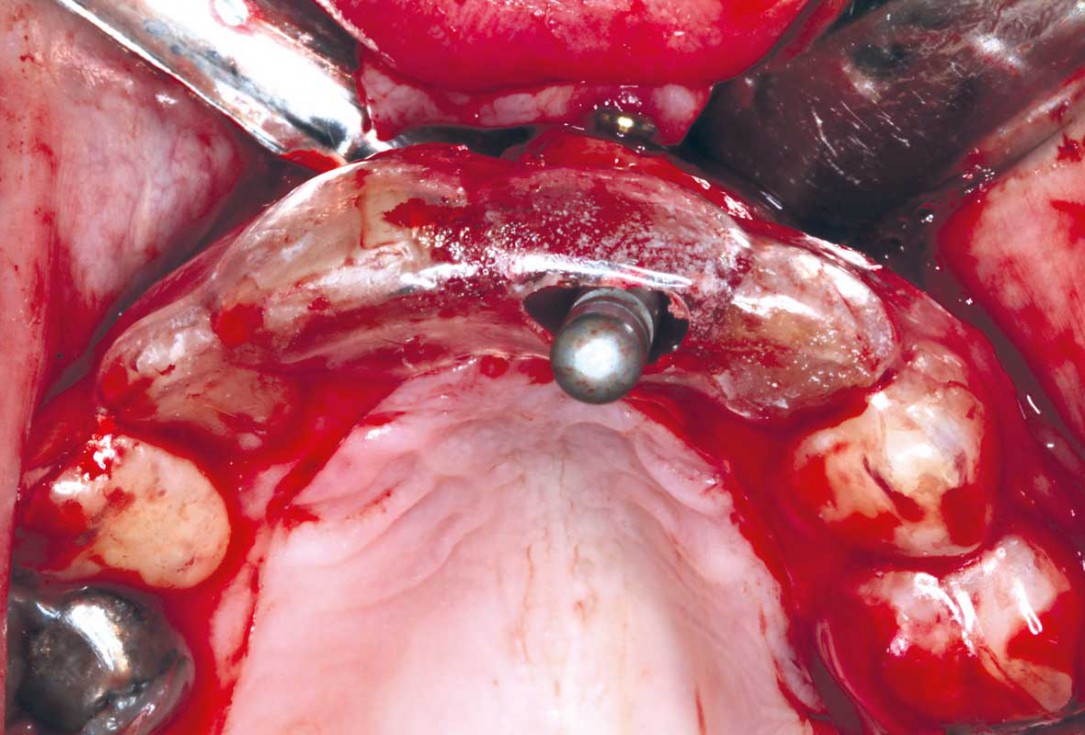

9/35 - Stabilisation of the bone block with two 10 mm fixation screws placed oblique. Sharp edges of the block were polished to avoid defeasance in the soft tissue healingBlock grafting in the aesthetic zone with maxgraft®, Jason® membrane and cerabone® - Dres. H. Maghaireh and V. Ivancheva

10/35 - Stabilisation of the bone block with two 10 mm fixation screws placed oblique. Sharp edges of the block were polished to avoid defeasance in the soft tissue healingBlock grafting in the aesthetic zone with maxgraft®, Jason® membrane and cerabone® - Dres. H. Maghaireh and V. Ivancheva